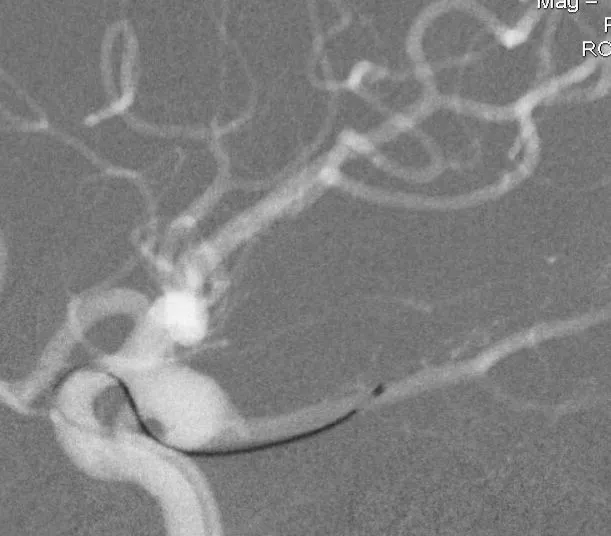

利用微导管的形状,将微导丝送入后交通动脉

微导丝走远

支架微导管到位

填了一个HydroFram8×30的弹簧圈成篮,从形态来看,应用双微导管技术栓塞是能够完成手术的

Enterprise4.5×22支架半释放,支架尾端的有效段能恰好覆盖全瘤颈

支架有效段完全释放,这个时候开始将支架导管往前顶,让导管头端尽量越过瘤颈远端

支架完全释放